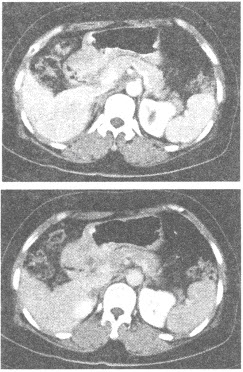

患者,女,56岁,上腹隐痛半年余,黑便。上腹部CT增强扫描图像如下,最有可能的诊断是()

A:胃癌

B:胃溃疡

C:慢性胃窦炎

D:胃淋巴瘤

E:胃间质瘤